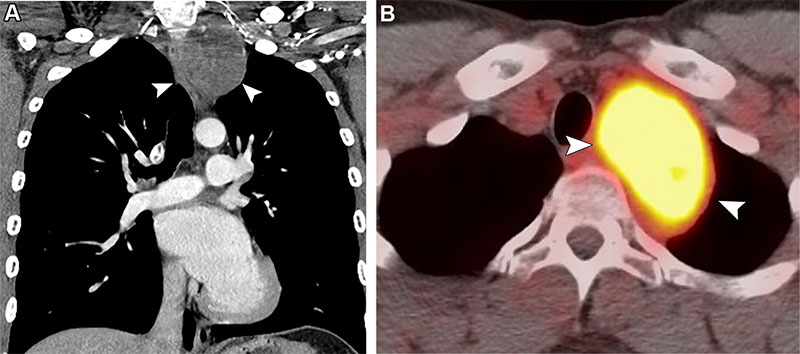

Post-RT malignancy in a 27-year-old man with a history of treated Hodgkin lymphoma and RT 12 years earlier.

Post-RT malignancy in a 27-year-old man with a history of treated Hodgkin lymphoma and RT 12 years earlier. Coronal CT (A) and axial FDG PET/CT (B) images show a well-defined mass (arrowheads) in the left upper mediastinum demonstrating intense FDG uptake without evidence of osseous invasion. Histopathologic examination results revealed a malignant peripheral nerve sheath tumor.